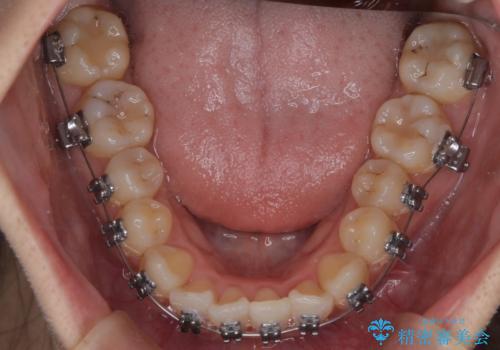

- 前歯のがたつきを治したいという主訴で来院されました。1年後に転勤の可能性があり短期間での治療を希望されました。今回は非抜歯の治療を計画し、IPRと拡大をし、前歯の叢生を改善しました。

前歯のがたつきを治しながら2番の反対咬合も改善させました。短期間で終了し満足していただけました。